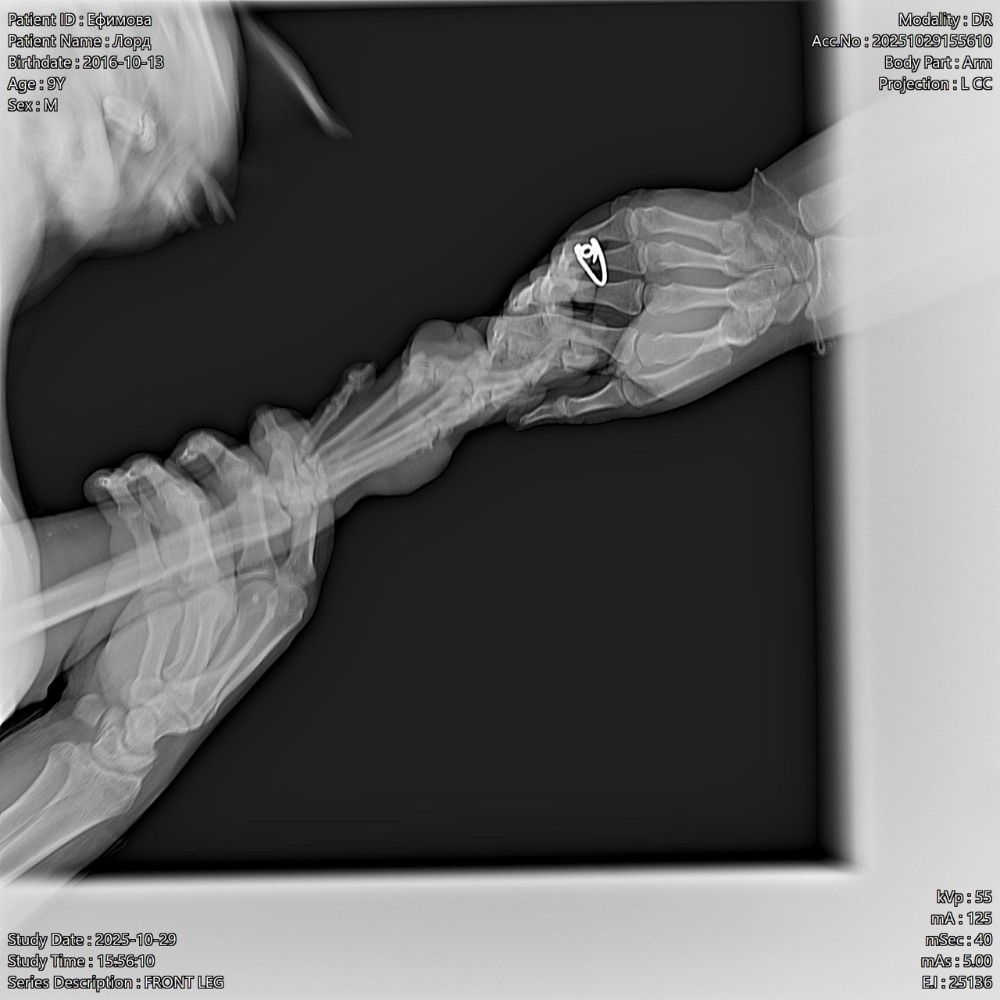

Всем привет, у меня собака лабрадор мальчик Лорд 9 лет. С детства на натуралке, месяц назад появилась шишка на лапе,  воспалилась лапа , которая у него по-видимому ноет и он ее разлизывает.

Ему сделали рентген ( фото прилагаю)

Он на лапу бывает хромает , и плюс еще дерматит межпальцевый пошел. Лапы после прогулки начала обрабатывать хлоргексидином.

Врачи толком ничего не говорят , что это может быть , подскажите пожалуйста, что это может быть(